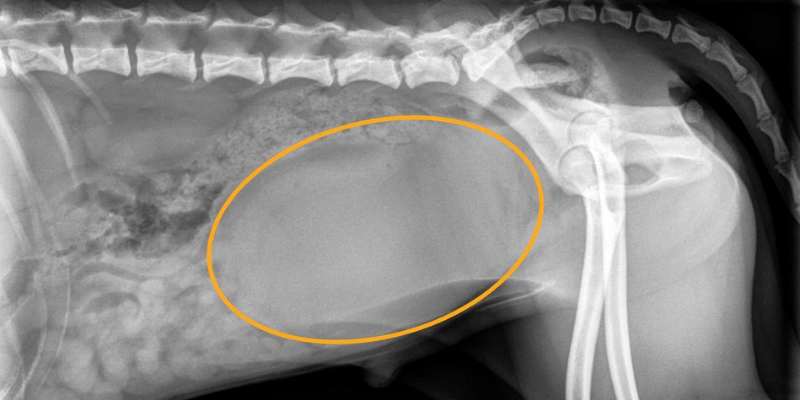

X-rays showed a very large bladder, but no clear cause for why he couldn’t urinate. (CLUE THREE).

X-rays showed no signs of stones, masses, or other structural changes that could explain Claude’s symptoms. Dr. Nevins, our board-certified veterinary radiologist, performed and interpreted an ultrasound of Claude’s entire urinary tract.

Since a PSS causes abnormal filtering and metabolism, pets are more prone to develop a special type of bladder stone called a urate stone. These stones caused Claude’s urinary obstruction. Since urate stones are made up of ammonia and uric acid, they cannot be seen on x-rays like most bladder stones (which is why they weren’t visible on Claude’s x-rays).